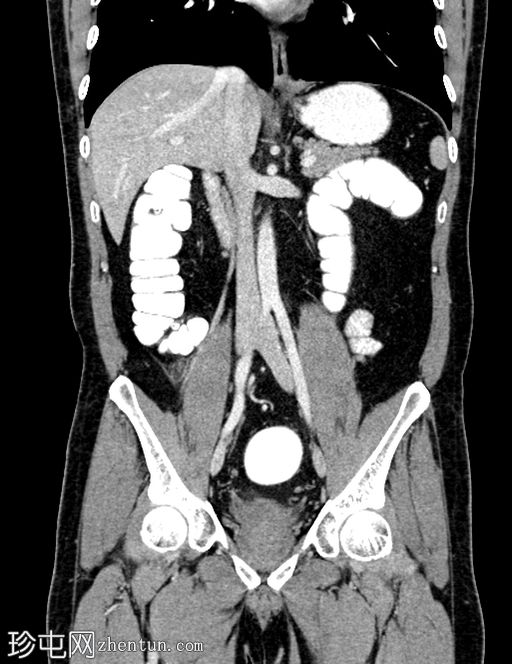

冠状位增强扫描

门静脉期

门静脉期,可见一持续存在的脂肪密度影,周围环绕高密度环;周围脂肪条索状改变,无脓肿形成,邻近结肠无憩室,盲肠壁正常。无阑尾炎,无淋巴结肿大,无游离气体或液体。